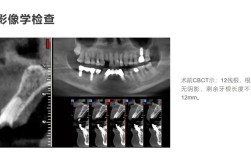

- 骨量(高度、宽度、密度): 这是种植体能否成功植入的关键,缺牙时间越长,牙槽骨吸收越严重,70岁老人通常存在不同程度的骨吸收,需要通过口腔锥形束CT(CBCT)进行精确评估。

- 拍摄口腔CBCT(三维影像)评估骨量骨质量。